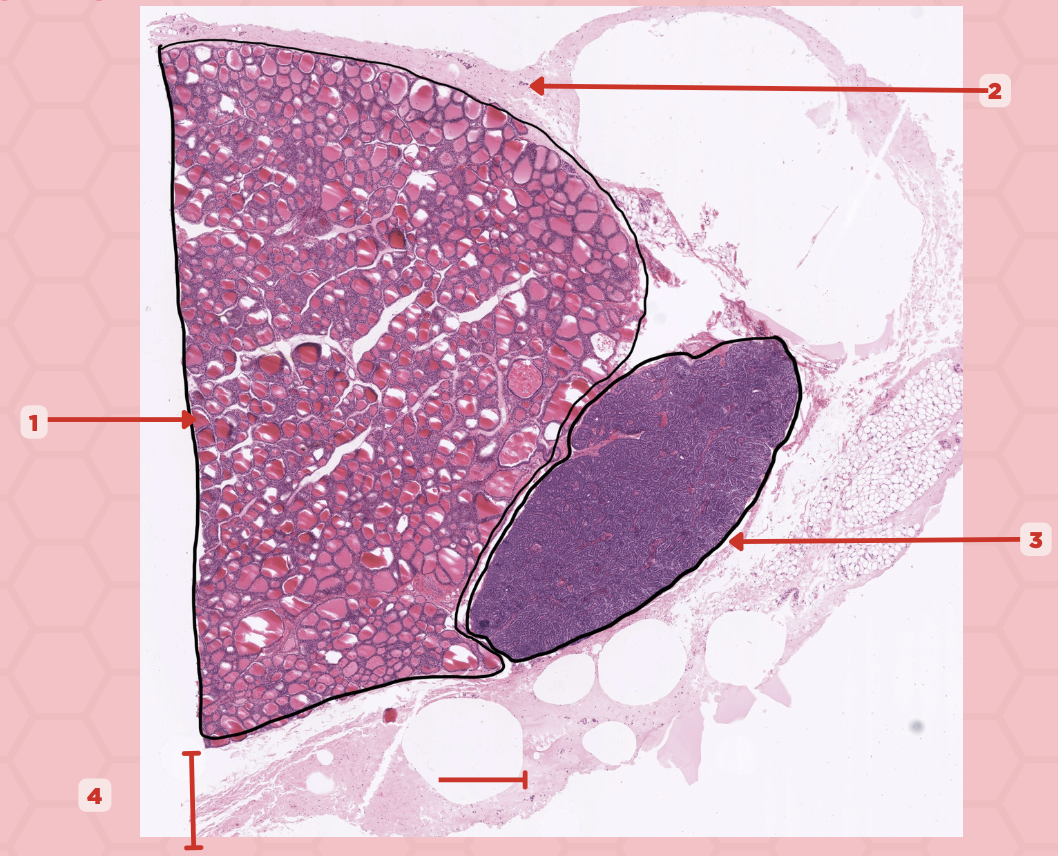

Parathyroid

Identify the specimen.

Chief Cells

Identify the structure labeled as 1. This comprise the majority of cells in the parathyroid gland.

Septa

Identify the structure labeled as 2.

Parathyroid

Identify the specimen.

Chief Cells

Identify the specimen labeled as 1.

Oxyphil Cells

Identify the specimen labeled as 2.

Adipocytes

Identify the specimen labeled as 3.

Capillaries

Identify the specimen labeled as 4.

Newborns

Pointer #2 is hardly present in the parathyroid glands of _____.

Parathyroid